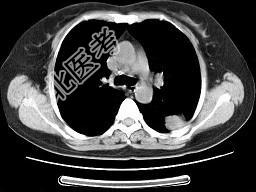

- 单项选择题女,52岁, 左侧背痛一月,胸部CT如图, 最可能的诊断为 ( )

A、左肺中央型肺癌

B、左肺周围型肺癌

C、左肺感染

D、左肺炎性假瘤

E、肺隔离征